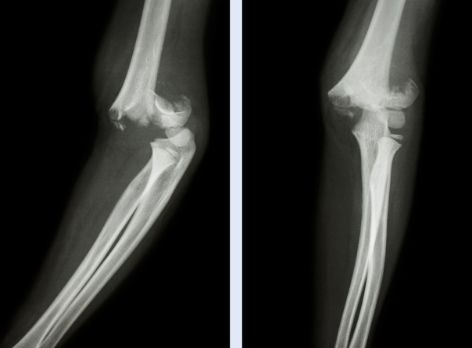

低硒会导致软骨坏死病变

目前已有大量研究表明,缺硒还会导致克山病,大骨节病的发生。这种以软骨坏死为主要病变的地方性、畸形性关骨关节病,与地方性缺硒有显著关系。其中,1985-1994年间,在甘肃省大骨节病活跃重病区吕家拉自然村,采用全民普食硒盐、儿童加服适量硒片的方法进行防治效果的观察。结果表明,补硒后儿童发硒由0.053pg/g,升高并稳定在0.237pg/g以上,儿童病情x线阳性检出率和阳性率由70.71%和57.58%降至0,病情得到有效控制。说明补硒防治措施对儿童大骨节病病变有显著的治疗效果,并有防治儿童发病的远期预防效果。